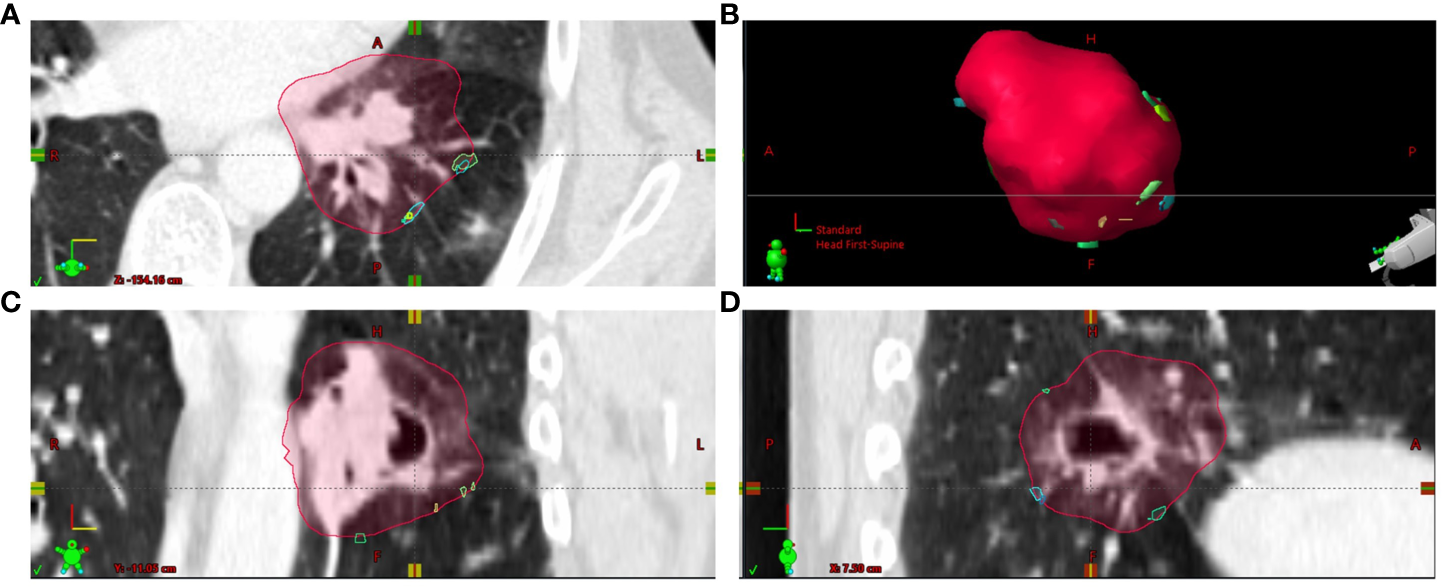

With respect to parameters characterizing the residual deformations of the CTVis, the Hausdorff distances (HDDi) as the maximum over the minimum distances between the deformed and original CTV borders were determined (Figure 4 new). Figure 5 depicts the empirical distribution functions (EDFs) for the HDDi values for different patients with significant differences from patient to patient (p < 0.0001, Kruskal–Wallis test). The median HDDi values for the different patients ranged from 3.0 to 7.0 mm.

Figure 4

The localizations of Hausdorff points from the different dose fractions i (HDPi) transferred to CTplan by deformable image registration are shown at the outer edge of the CTVplan contour for patient (A) Most HDPi on the CTVplan contour were inferior to the CTVplan center. (A) Axial plane through CTVplan; (B) 3D view on CTVplan surface; (C) frontal plane through CTVplan; (D) sagittal plane through CTVplan.